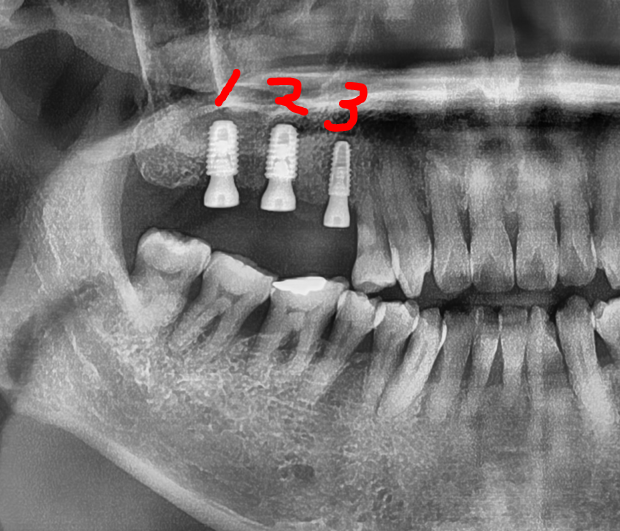

사진에서 보실 수 있는 것 처럼 먼저 3개의 고정체를 심었습니다.